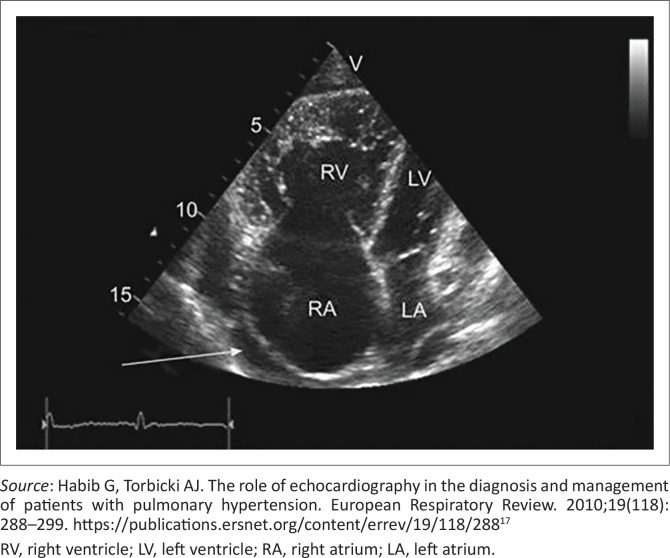

Heart failure poses a significant global health challenge, with a considerable burden in Africa, where the annual mortality rate stands at 34%, twice the global average. Patients suffering from acute heart failure occupy numerous beds at the district level, and only a limited number can be referred for further evaluation and imaging at secondary or tertiary care facilities. Patients rely on their primary care physicians for the diagnosis and management of heart failure, as well as for identifying those who would benefit from referral to cardiology and formal echocardiography. This article discusses the significance of the new heart failure guidelines within the South African primary care public setting. It emphasises the importance of identifying risk factors and considers the value of access to family physicians, outreach clinic doctors, training on available adult primary care guidelines and telemedicine-supported cardiac ultrasound. Optimal medical therapy, which includes angiotensin-converting enzyme (ACE) inhibitors, beta-blockers and spironolactone, has been shown to reduce readmissions and mortality rates. Sodium-glucose cotransporter-2 (SGLT2) inhibitors are a potent addition to conventional therapy and are currently being considered for inclusion in the National Essential Medicines List. Patients admitted to the hospital should not be discharged while experiencing persistent congestion, as this is associated with an increased risk of rehospitalisation, mortality and higher healthcare costs. Comprehensive patient education regarding medications, thorough follow-up during the six weeks post-discharge and linkage to primary healthcare are associated with decreased hospitalisation rates and improved outcomes.